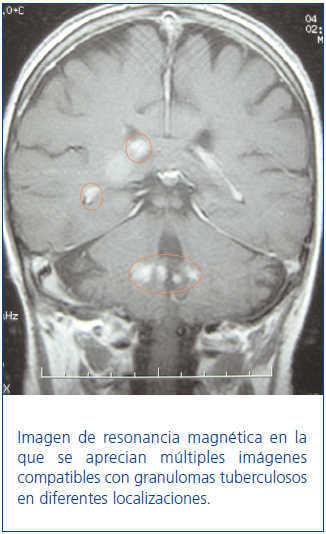

Mujer de 66 años, con insuficiencia renal crónica secundaria a poliquistosis hepatorrenal, que recibió un trasplante renal de cadáver y tratamiento con baxilisimab, esteroides, micofenolato mofetil y tacrolimus. Sufrió un rechazo agudo tipo IIb córtico-resistente que precisó tratamiento con OKT3. A los cuatro meses ingresó por fiebre, malestar general y astenia intensa. Fue diagnosticada de tuberculosis pulmonar sospechada por tomografía computarizada (TC) torácica y fibrobroncoscopia y confirmada por tinción de Ziehl-Neelsen y cultivo de Löwenstein. Se pautó tratamiento con rifampicina, isoniazida y piracinamida durante dos meses, y rifampicina e isoniazida cuatro meses más. A los 15 días reingresó por confusión, cefalea occipital y alteraciones visuales. En una resonancia cerebral se vieron múltiples nódulos hiperintensos en T2, con realce focal nodular, en áreas frontal derecha, subcortical, suprasilviana, occipital derecha y en pedúnculos cerebelosos, indicativos de infiltración granulomatosa secundaria a tuberculosis (figura 1). El tratamiento con isoniazida y rifampicina se amplió hasta nueve meses y consiguió la recuperación de la paciente.

Figura 1. Tuberculomas cerebrales.